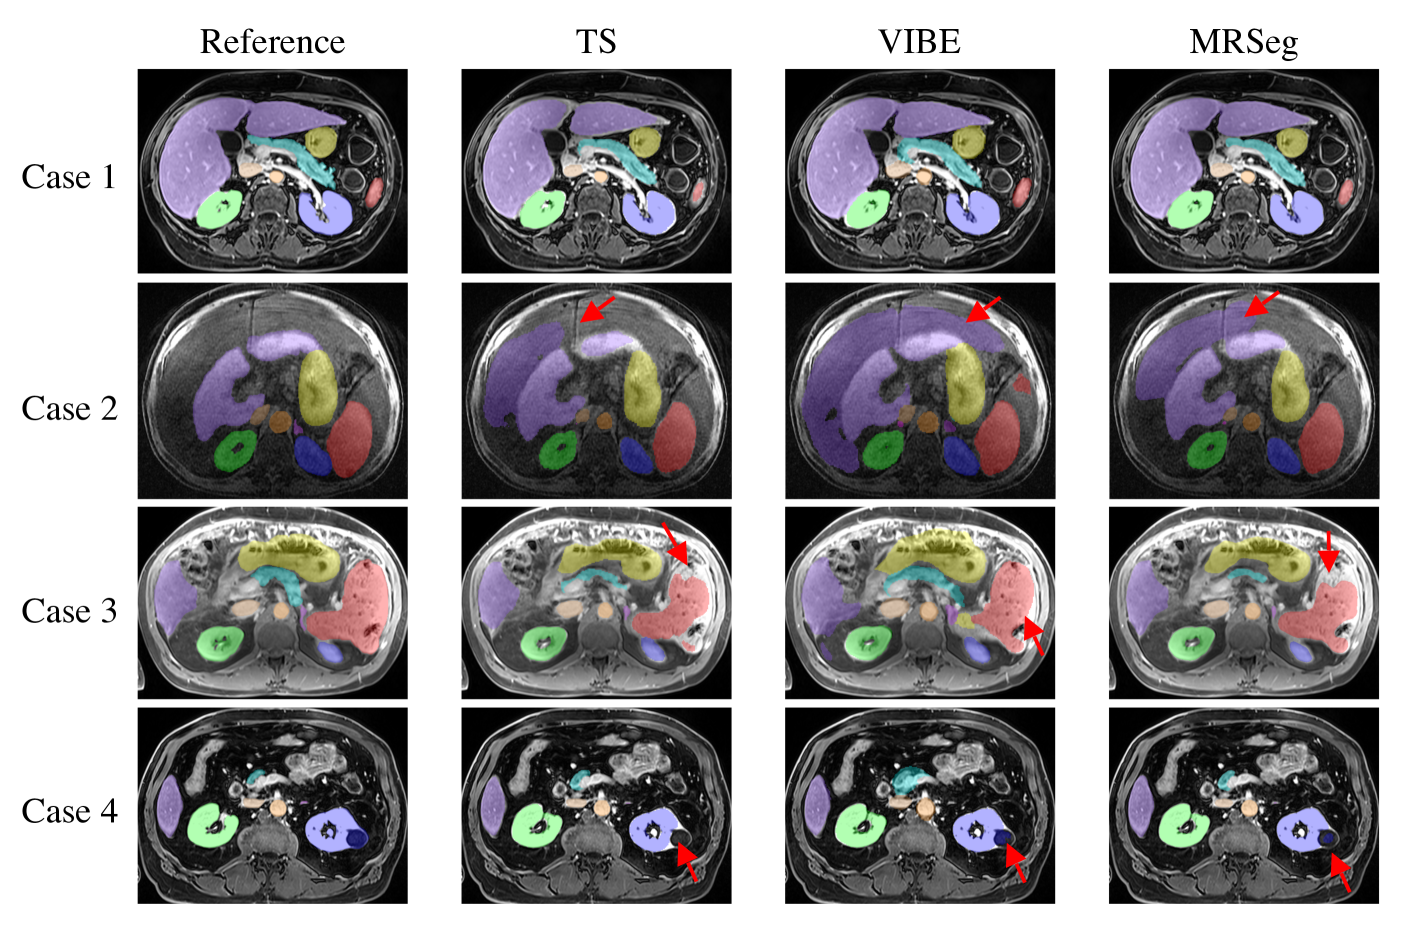

Fig. 3 visually illustrates the segmentation results by the three segmentation tools for a few cases. All the tools struggled with the pathologies present in the Duke Liver Dataset, such as cirrhosis or the presence of kidney lesions, tending to undersegment in the case of lesions and oversegment in the case of cirrhosis. The performance of the three tools on each of the 10 structures are shown in Supplemental Figs. 4 to 9. MRSeg consistently obtained the highest DSC and lowest HD errors for large organs (liver, spleen, stomach), medium-sized organs (kidneys and pancreas), and small organs (adrenal glands, aorta and inferior vena cava). Notably, MRSeg segmented the pancreas and the aorta better than TS and VIBE. VIBE had the highest HD errors across all structures; the error was greatest mainly for the stomach, aorta, and pancreas.

All the tools over-segmented the liver and encroached into the adjacent Ascites (fluid buildup around the liver) as seen in Fig. 3. Notably, they under-segmented the pancreas and the adrenal glands, and did not segment lesions and cysts if they were present in certain organs, such as the spleen and kidneys. It is important to note that there were missing organs in two pre-contrast series; the left adrenal gland was missing from one series, while the right kidney was removed from another pre-contrast series. These missing organs were accounted for and the presented results are shown for those organs that were available. TS and VIBE had false positive segmentations for these missing structures as shown in Supplemental Fig. 10.

Refer to caption

Figure 3: Comparison of multi-organ segmentations by TS, VIBE, and MRSeg for four different patients containing various disease conditions. Case 1 shows a normal patient with no disease. Case 2 shows a patient with liver cirrhosis. Note the over-segmentation of the liver into adjacent ascites (fluid region, red arrows). Case 3 shows a patient with multiple splenic lesions (red arrows). Case 4 shows a patient with a lesion in the left kidney.